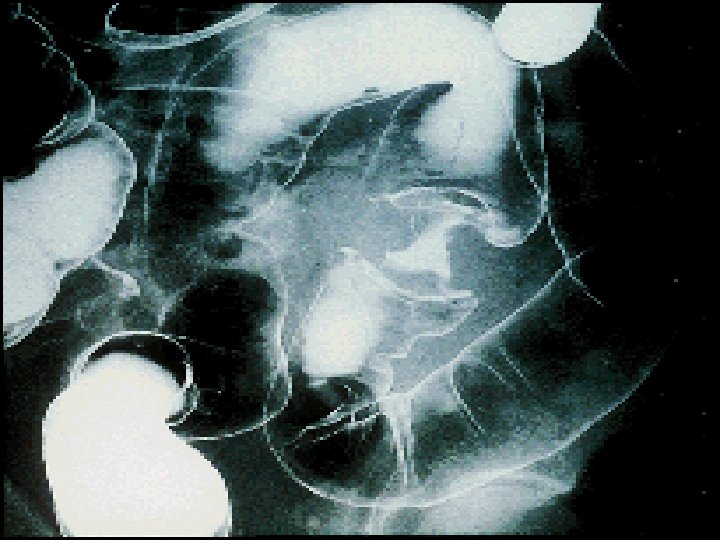

Diseases Of The Colon Professor Dr Sabeha Al

Tumors Of The Colon Rectum Polyps Polyposis Syndrome